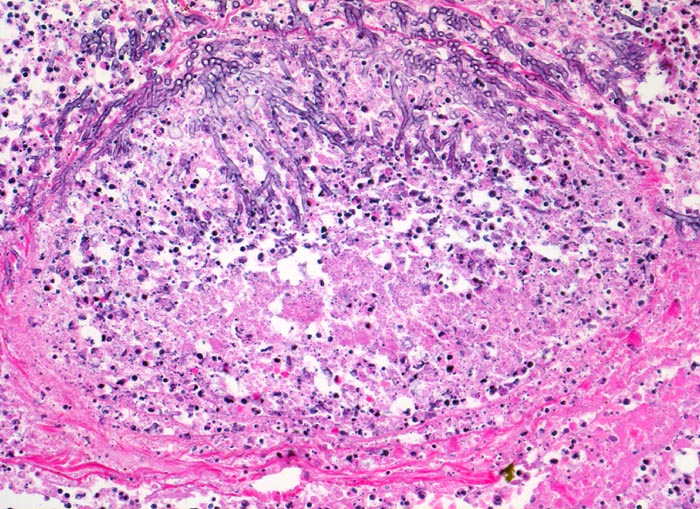

Gewebsnekrose durchsetzt von zerfallenden neutrophilen Granulozyten (die schwarzen Punkte entsprechen den Kerntrümmern der neutrophilen Granulozyten). In der Nekrose sind schlanke Pilzhyphen mit 45° Verzweigungen erkennbar.

Seit 14 Monaten bekannte chronische lymphatische Leukämie behandelt mit Chemotherapie. Der Patient entwickelt unter Therapie eine Pneumonie und verstirbt an einer Pilzsepsis.